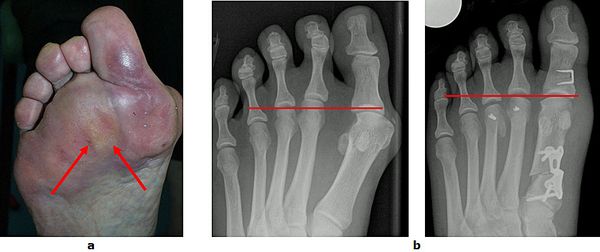

Abb.10: a Schmerzhafte Schwielenbildung unter dem Vorfuß.

b Wiederherstellung der Längenverhältnisse zwischen dem ersten, zweiten und dritten Strahl durch eine Rückverlagerung der Mittelfußköpfchen zwei und drei. Zeitgleich wurde auch der Hallux valgus korrigiert.